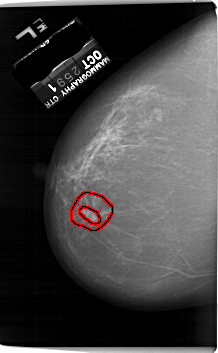

A_1253_1.LEFT_MLO

LEFT_MLO LINES 6691 PIXELS_PER_LINE 4411 BITS_PER_PIXEL 12 RESOLUTION 43.5 OVERLAY

FILE: A_1253_1.LEFT_MLO.OVERLAY

TOTAL_ABNORMALITIES 1

ABNORMALITY 1

LESION_TYPE MASS SHAPE IRREGULAR MARGINS ILL_DEFINED

ASSESSMENT 4

SUBTLETY 2

PATHOLOGY MALIGNANT

TOTAL_OUTLINES 2

BOUNDARY

CORE